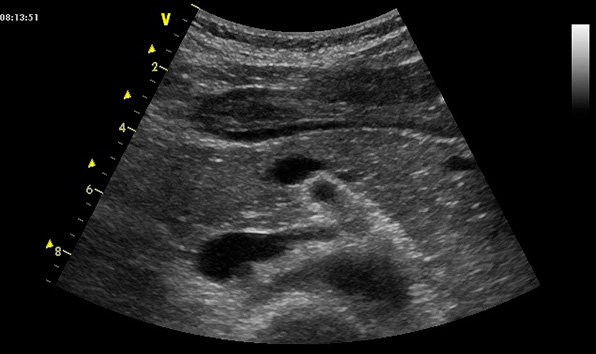

Ультразвуковое исследование поджелудочной железы является безопасным и информативным методом диагностики, позволяющим выявить воспалительные и травматические изменения, а также опухоли. Обычно исследование проводится в положении на спине, при этом датчик устанавливается в эпигастральной области поперечно.

На фиксированном вдохе или выдохе (оптимально – при надувании живота) врачу удается лучше визуализировать железу. В некоторых случаях, из-за значительного подкожно-жирового слоя или метеоризма, удается увидеть только головку и тело органа.

Ультразвуковое изображение неизмененной железы может иметь различный вид, как по своей эхогенности, так и по своей структуре. Следует помнить, что эхогенность нормальной поджелудочной приравнивается к таковой у печени, однако может быть несколько выше или ниже ее. Важный критерий – плотность органа не должна превышать плотность окружающей его жировой клетчатки (на УЗИ она «белая»).

Паренхима поджелудочной мелко- либо крупнозернистая, иногда с тонкими гиперэхогенными прослойками в виде «разрезанного мяса», что врачи-сонологи ошибочно принимают за признаки хронического панкреатита. У пожилых людей ее эхогенность практически приравнивается к эхогенности окружающей клетчатки за счет естественных возрастных изменений. При этом контуры поджелудочной железы неровные и нечеткие.

В небольшом количестве случаев Вирсунгов проток может быть незначительно расширен и у здоровых людей (через него железа выбрасывает свои ферменты в просвет двенадцатиперстной кишки). Не стоит забывать, что УЗИ – это операторозависимый метод диагностики, поэтому иногда возникают сложности в интерпретации полученных данных.